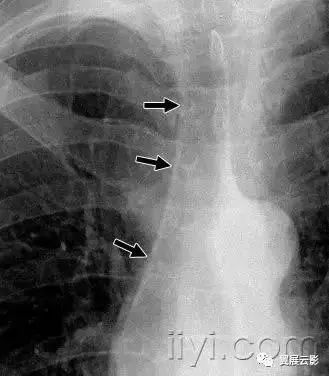

病理:纵隔气肿是指气体存在于食管和气管支气管树之外的纵隔组织内,可以是肺泡的自发破裂导致气体沿着气管血管间质进入纵隔所致。纵隔气肿与哮喘、重度咳嗽,或者机械通气有着明显联系。

平片和CT:纵隔气肿在胸片上显示为带状的透亮影,大多数垂直走向,见图。部分低信号条带影可以勾勒出血管和支气管的边界(参加心包气肿)